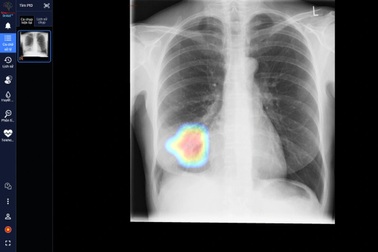

DrAid - công cụ sàng lọc và tiên lượng Covid-19 ứng dụng AI đầu tiên tại Việt NamDrAid cho Covid-19 - sản phẩm ứng dụng trí tuệ nhân tạo (AI) của Công ty Cổ phần VinBrain (thuộc Tập đoàn Vingroup) - vừa được Hội đồng Khoa học Bộ Y tế nghiệm thu và kiến nghị nên sớm đưa vào sử dụng tại các bệnh viện.

DrAid và hành trình bền bỉ mang AI từ nghiên cứu tới tay 1.000 bác sĩ trên khắp Việt NamDrAid - phần mềm chẩn đoán hình ảnh y tế do VinBrain (Tập đoàn Vingroup) nghiên cứu, phát triển dựa trên bộ dữ liệu lớn nhất Việt Nam gồm 1,3 triệu hình ảnh X-quang với sự tham gia của gần 1.000 bác sĩ tại hơn 100 bệnh viện.

Gặt hái "quả ngọt" khi công nghệ "bắt tay" cùng y tế11.000 ảnh X-quang bệnh nhân Covid-19 được thu thập từ 26 khu cách ly tại Bắc Giang và TPHCM chỉ trong 2 tháng, với số lượng nhân sự chỉ đếm trên đầu ngón tay, các thành viên VinBrain đã "gặt hái quả ngọt" trong những nỗ lực hướng đến cộng đồng.